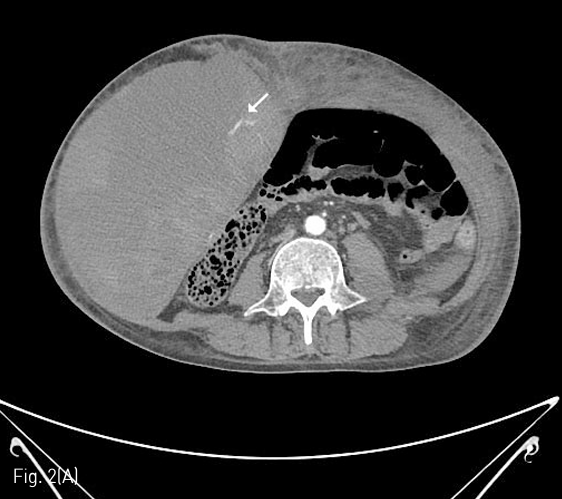

Fig 2A

(A) 7 days later, marked increase of size of the abdominal wall hematoma (about 26 x 12cm) was noted on follow-up abdomen CT, and another active bleeding focus from the right inferior epigastric artery was noted.

Fig 2B

(B) Multifocal extravasation of contrast media from the small branches on right inferior epigastric angiography could be noted(arrows), and glue embolization was performed.